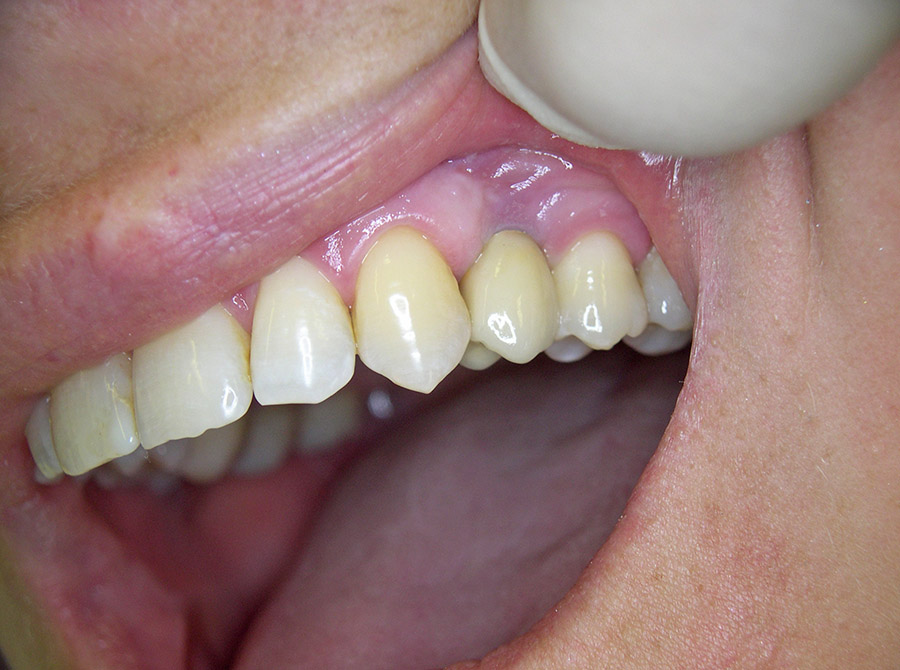

Ein besonderer positiver Effekt der Implantate ist, dass sie den Kieferknochen und das Zahnfleisch erhalten, während sich der Knochen unter Brücken und Prothesen hingegen abbaut. In vielen Fällen lässt sich so die natürliche Rot-Weiß-Ästhetik, also das harmonische Zusammenspiel von Zahnfleisch und Zähnen erhalten, so dass implantat-getragene Kronen kaum von eigenen gesunden Zähnen zu unterscheiden sind.